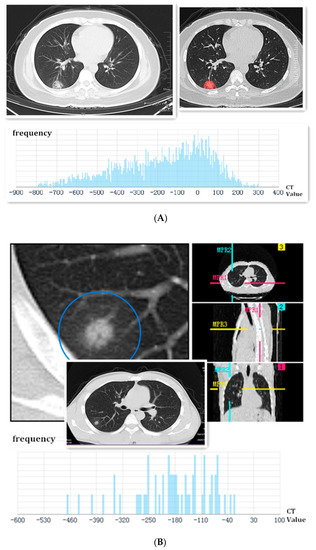

| Density of the SPN | |

| Pure ground-glass nodule | 13 (61.9%) |

| Mixed ground-glass nodule | 8 (38.1%) |